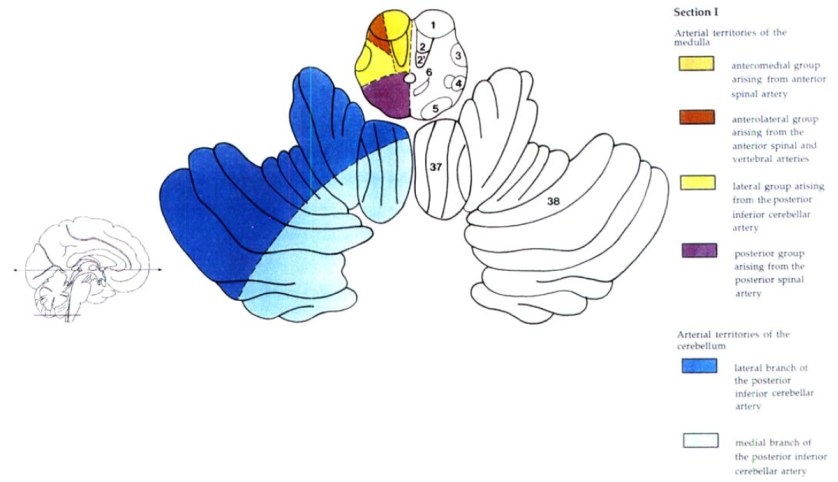

Cerebral vascular territories

Brainstem